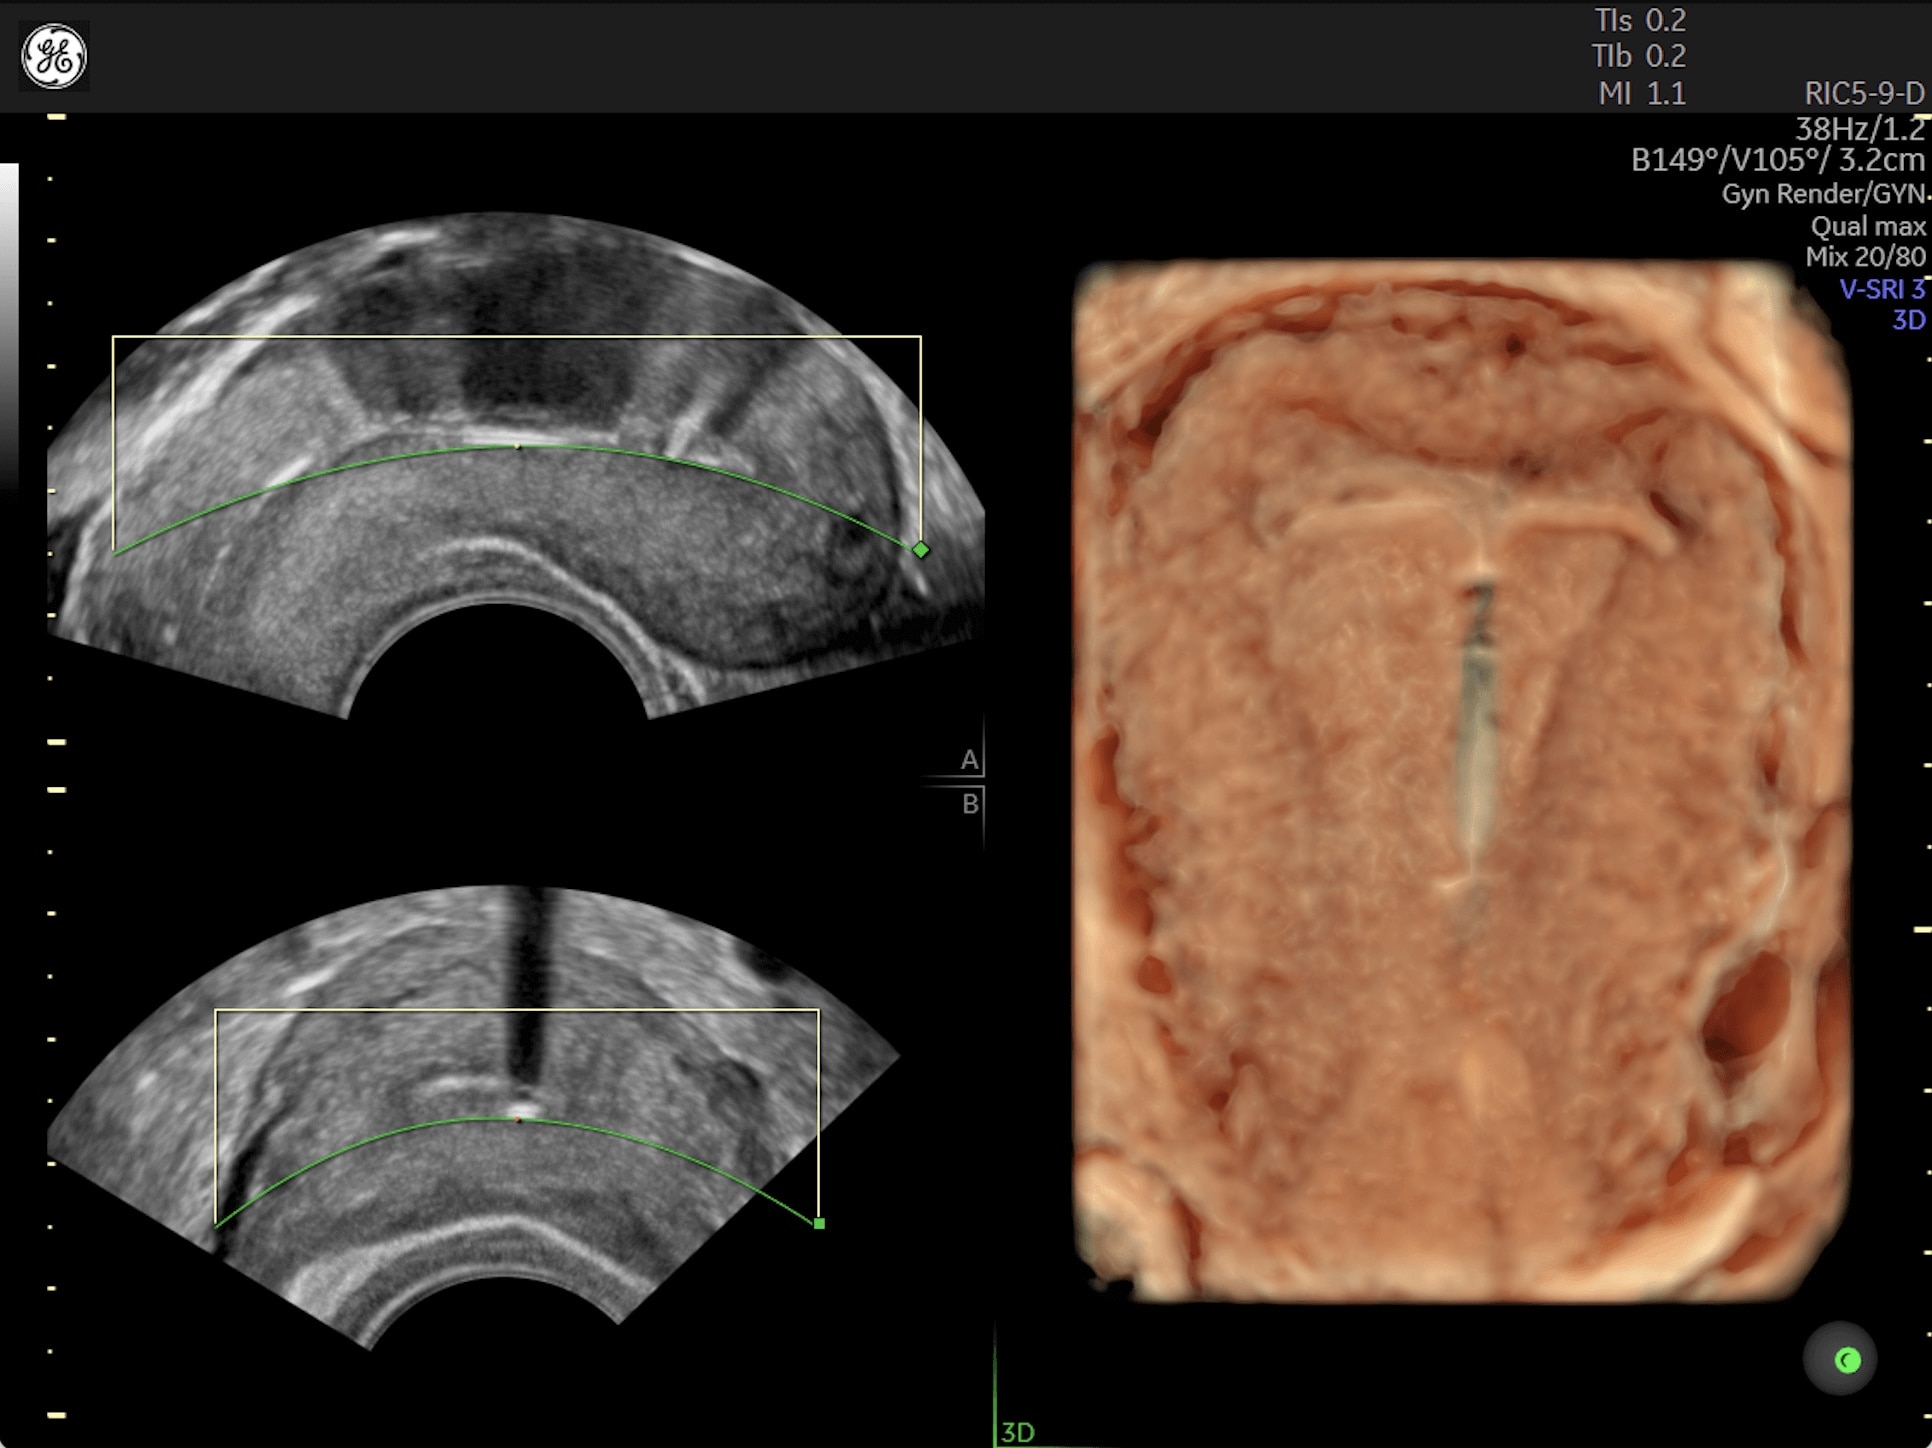

Generate spectacular 2D/3D and color Doppler images with increased penetration and stunning clarity, to help visualize critical details needed for diagnostic assurance. The Lyric Architecture unlocks new imaging and processing power to expand your imaging capabilities for years to come